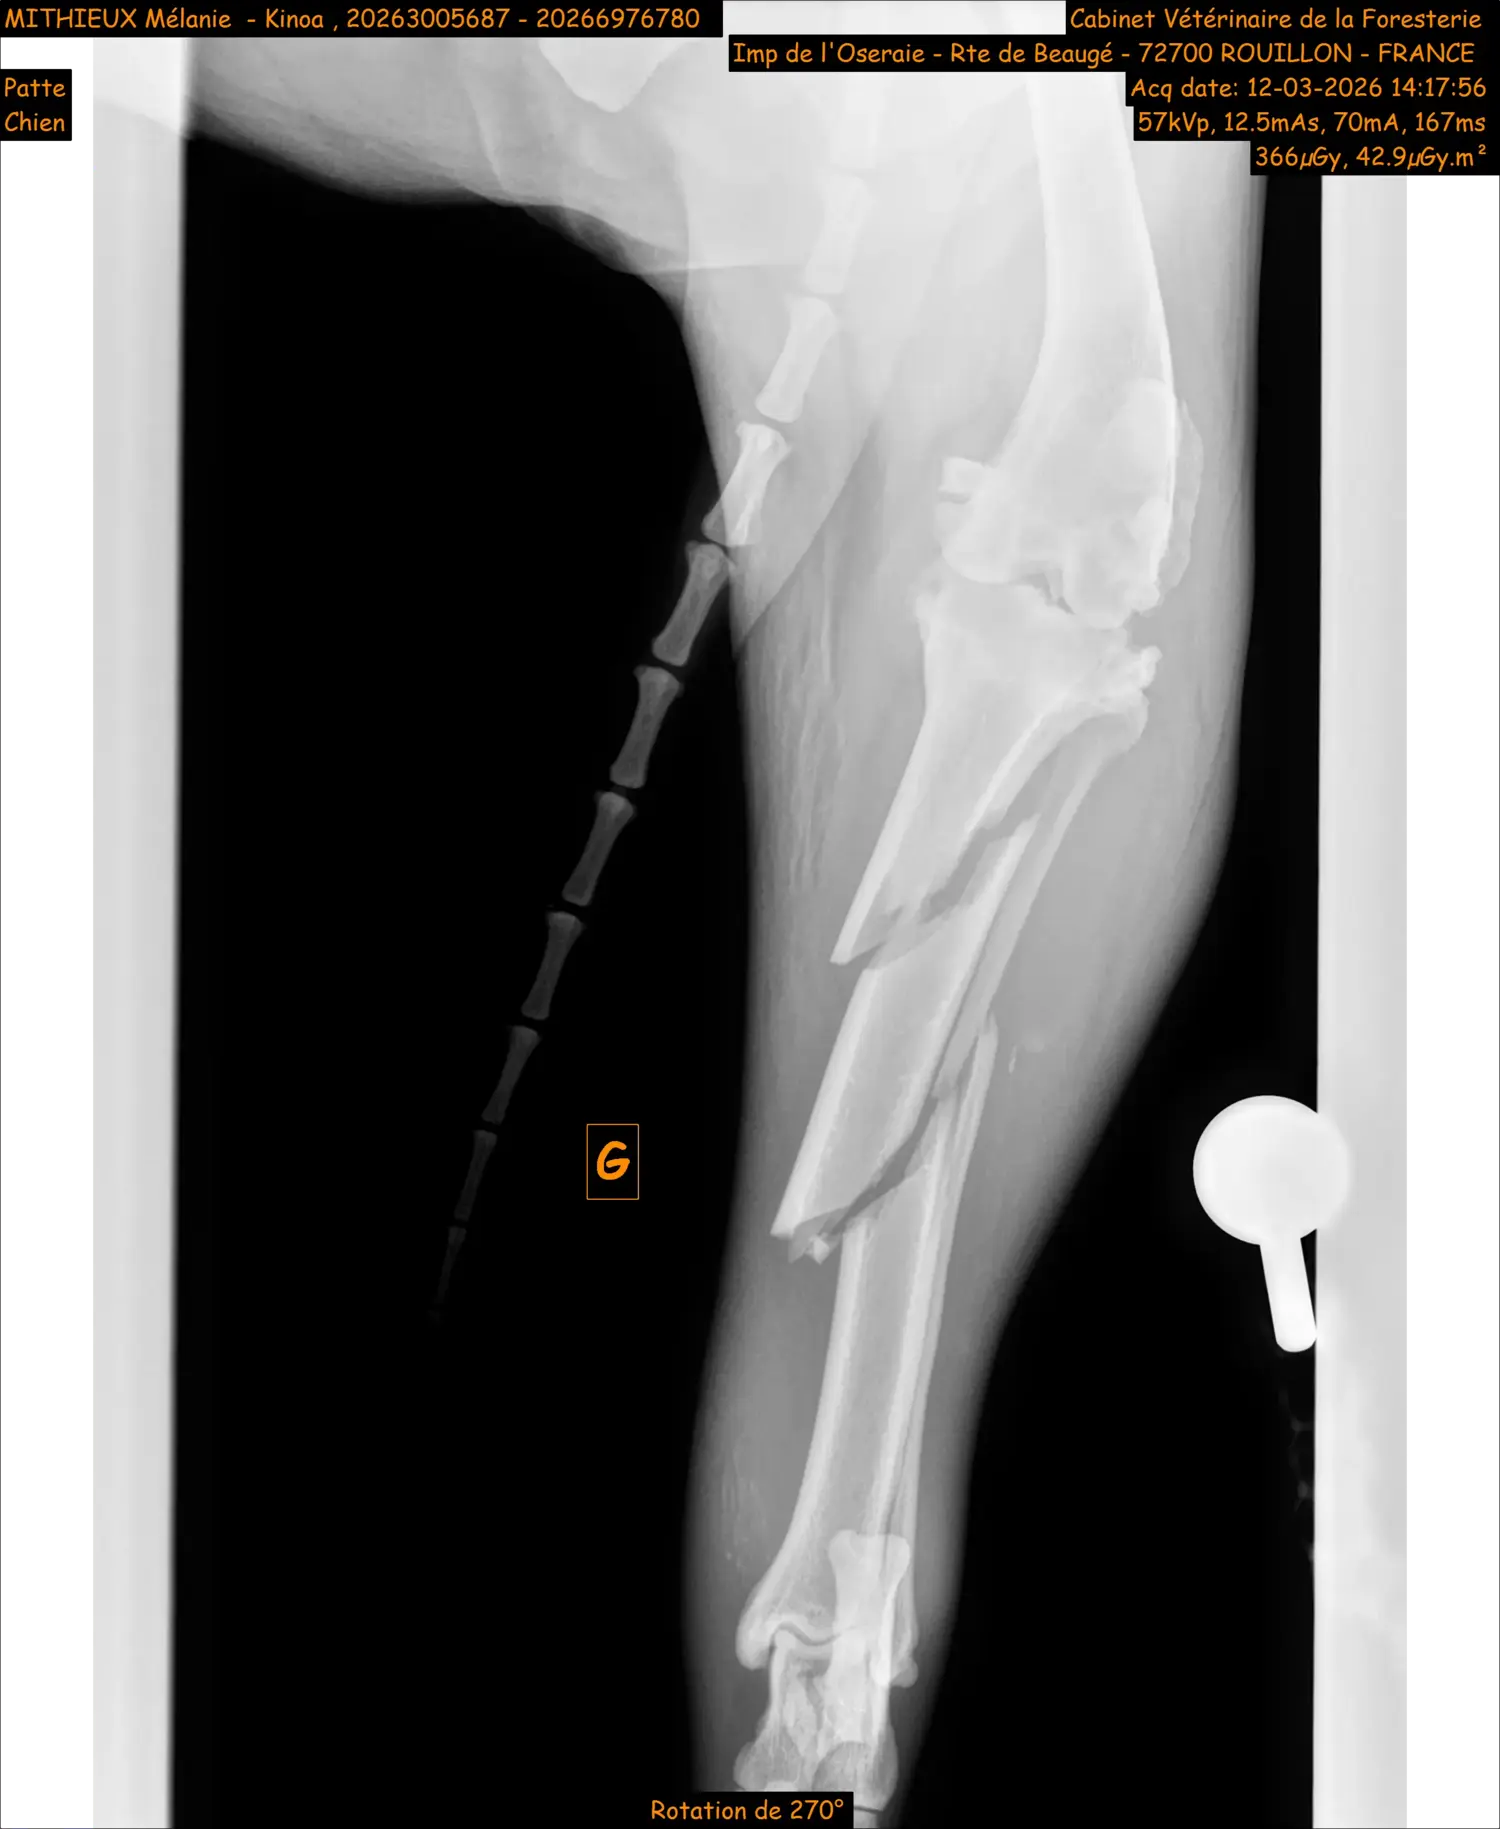

Les chirurgies orthopédiques sont régulières au sein de la clinique. Elles nécessitent une technique et du matériel chirurgical bien spécifiques. Il s’agit le plus souvent de réduction de fracture ou de luxation, rupture du ligament croisé antérieur (TPLO), luxation de rotule,…